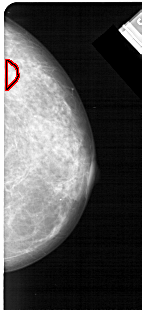

FILE: A_1473_1.RIGHT_MLO.OVERLAY

TOTAL_ABNORMALITIES 1

ABNORMALITY 1

LESION_TYPE MASS SHAPE IRREGULAR MARGINS ILL_DEFINED

ASSESSMENT 4

SUBTLETY 3

PATHOLOGY BENIGN

TOTAL_OUTLINES 1

BOUNDARY